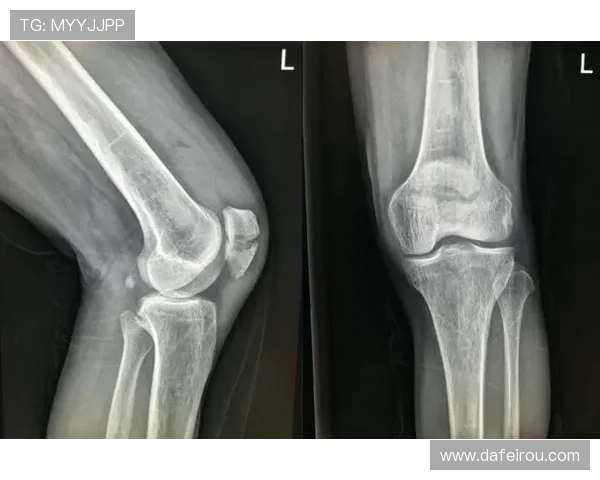

法比安的左膝髌骨裂伤情是他无法出战的主要原因之一。膝盖髌骨裂伤是一种需要长时间休养和逐步康复的伤病,尤其对于职业运动员来说,恢复过程要求精细的医学干预和系统的康复训练。尽管他已经开始进行一定的康复训练,但医务团队认为伤情尚未完全恢复,过早投入比赛可能会导致更严重的后遗症。

法比安的膝盖伤情复原需要更长时间的积累,恢复的每一个细节都至关重要。如果没有充分的恢复,法比安不仅会面临持续的疼痛,还可能影响到日后的职业生涯。因此,医生和团队共同决定让他继续休养,确保伤情得到完全治愈后再考虑复出。

法比安个人的康复进展也是决定他是否复出的关键因素之一。根据队医的评估,法比安的康复虽然在稳步推进,但依然需要额外的时间来增强膝部肌肉的稳定性,以避免再次受伤。他的康复过程包括低强度的物理治疗和逐步增加运动负荷,确保膝盖在完全恢复之前不会受到过度的压力。

法比安自己也非常关注自己的康复进程,他通过与队医和康复专家的密切合作,确保每一个步骤都符合最优的恢复方案。在未来几周,他将继续接受专业的训练,并按照医嘱调整运动强度,力求尽快复原,以便在伤情完全恢复后能够重返赛场。